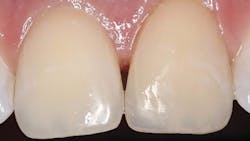

A 20-year-old male presented with numerous class V decalcification lesions, some of which extended through the enamel and required a direct restorative approach (figure 1). After anesthesia was obtained, removal of the caries with a pear-shaped carbide bur (#330 NeoBurr, Microcopy Dental) was completed. An enamel bevel of 2–3 mm with an irregular outline was placed with a 45u flame-shaped diamond (209.6 VF, Premier Dental) to facilitate enamel etching and blending of the composite. The preparation was isolated using a clear Mylar-based matrix (Margin Perfect Matrix). A total-etch technique was employed, followed by the use of a universal bonding agent (Tokuyama Universal Bond, Tokuyama Dental America) according to the manufacturer’s instructions. A single application of Omnichroma was expressed and manipulated with composite instruments and brushes prior to curing with an LED light source for 20 seconds. Once the matrix was removed, finishing was accomplished with 12 fluted spiral-bladed carbide burs (H48L-010, H274-016, Brasseler USA), and final polish was achieved with a series of abrasive cups and points (Astropol, Ivoclar/Vivadent) to a final luster (figure 2).